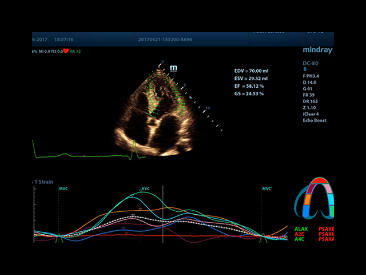

TT QA (vector)